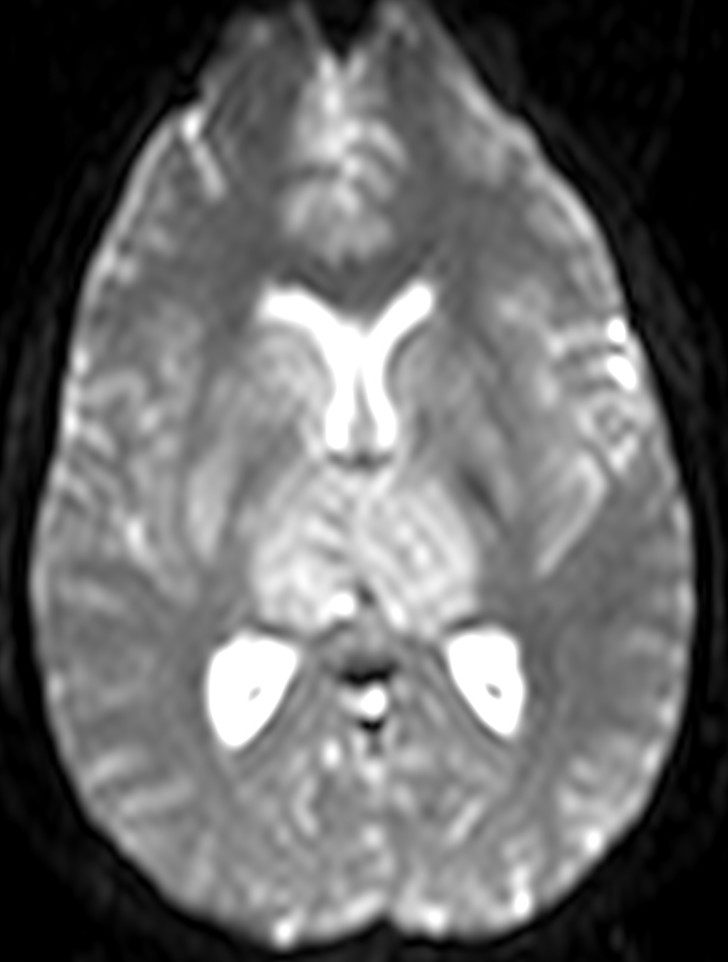

Se decide realizar una RM y una venografía RM para descartar una TVC. Ante el mal estado de la paciente, la cual no colabora, solo se puede terminar realizando secuencias FLAIR y Difusión.

Secuencia de Difusión:

El patrón de edema es heterogéno, como el árbol venoso vascular. Primero se produce un edema citotóxico y luego vasogénico. El edema citotóxico se ve hiperintenso en Difusión e hipointenso en los mapas de coeficiente de dicusión aparente (CDA). El edema vasogénico se ve iso/hiperintenso en Difusión e hiperintenso en CDA.

La Difusión puede usarse para valorar la evolución del trombo. Los trombos que con el tiempo de evolución no muestran hiperintensidad de señal en difusión, presentan tasas de recanaliazación de hasta el 88%.